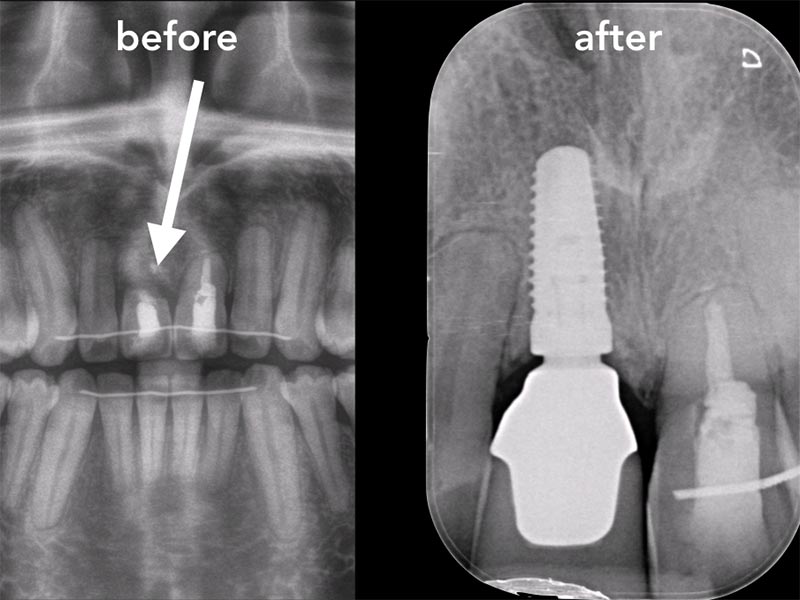

Zahnimplantate werden anhand von moderner virtueller 3D-Planung passgenau geplant und inseriert. Der Vorteil von Implantaten besteht darin, dass festsitzender ästhetischer Zahnersatz auch in solchen Fällen realisiert werden kann, in denen sonst nur herausnehmbare Prothesen möglich wären. Zudem ist im Gegensatz zur Brückenprothetik kein Beschleifen der Nachbarzähne notwendig.

Unter dentalen Implantaten versteht man im allgemeinen eine Schraube, die dort, wo ein oder mehrere Zähne verloren gegangen sind, in den Kieferknochen "eingepflanzt" wird. Diese Therapieform der Implantologie hat sich in den letzten Jahren zu einem alltäglichen Therapieverfahren in der Zahnheilkunde entwickelt. Wissenschaftliche Untersuchungen zeigen hierfür eine Erfolgsquote von i. d. R. 80-98 % über 10 Jahre. Verglichen mit anderen zahnärztlichen Maßnahmen gibt es nahezu keine andere Therapie mit derart guten Erfolgsaussichten. Auch eine Verbesserung der Lebensqualität wird durch implantatgetragenen Zahnersatz laut klinischer Studien erreicht.